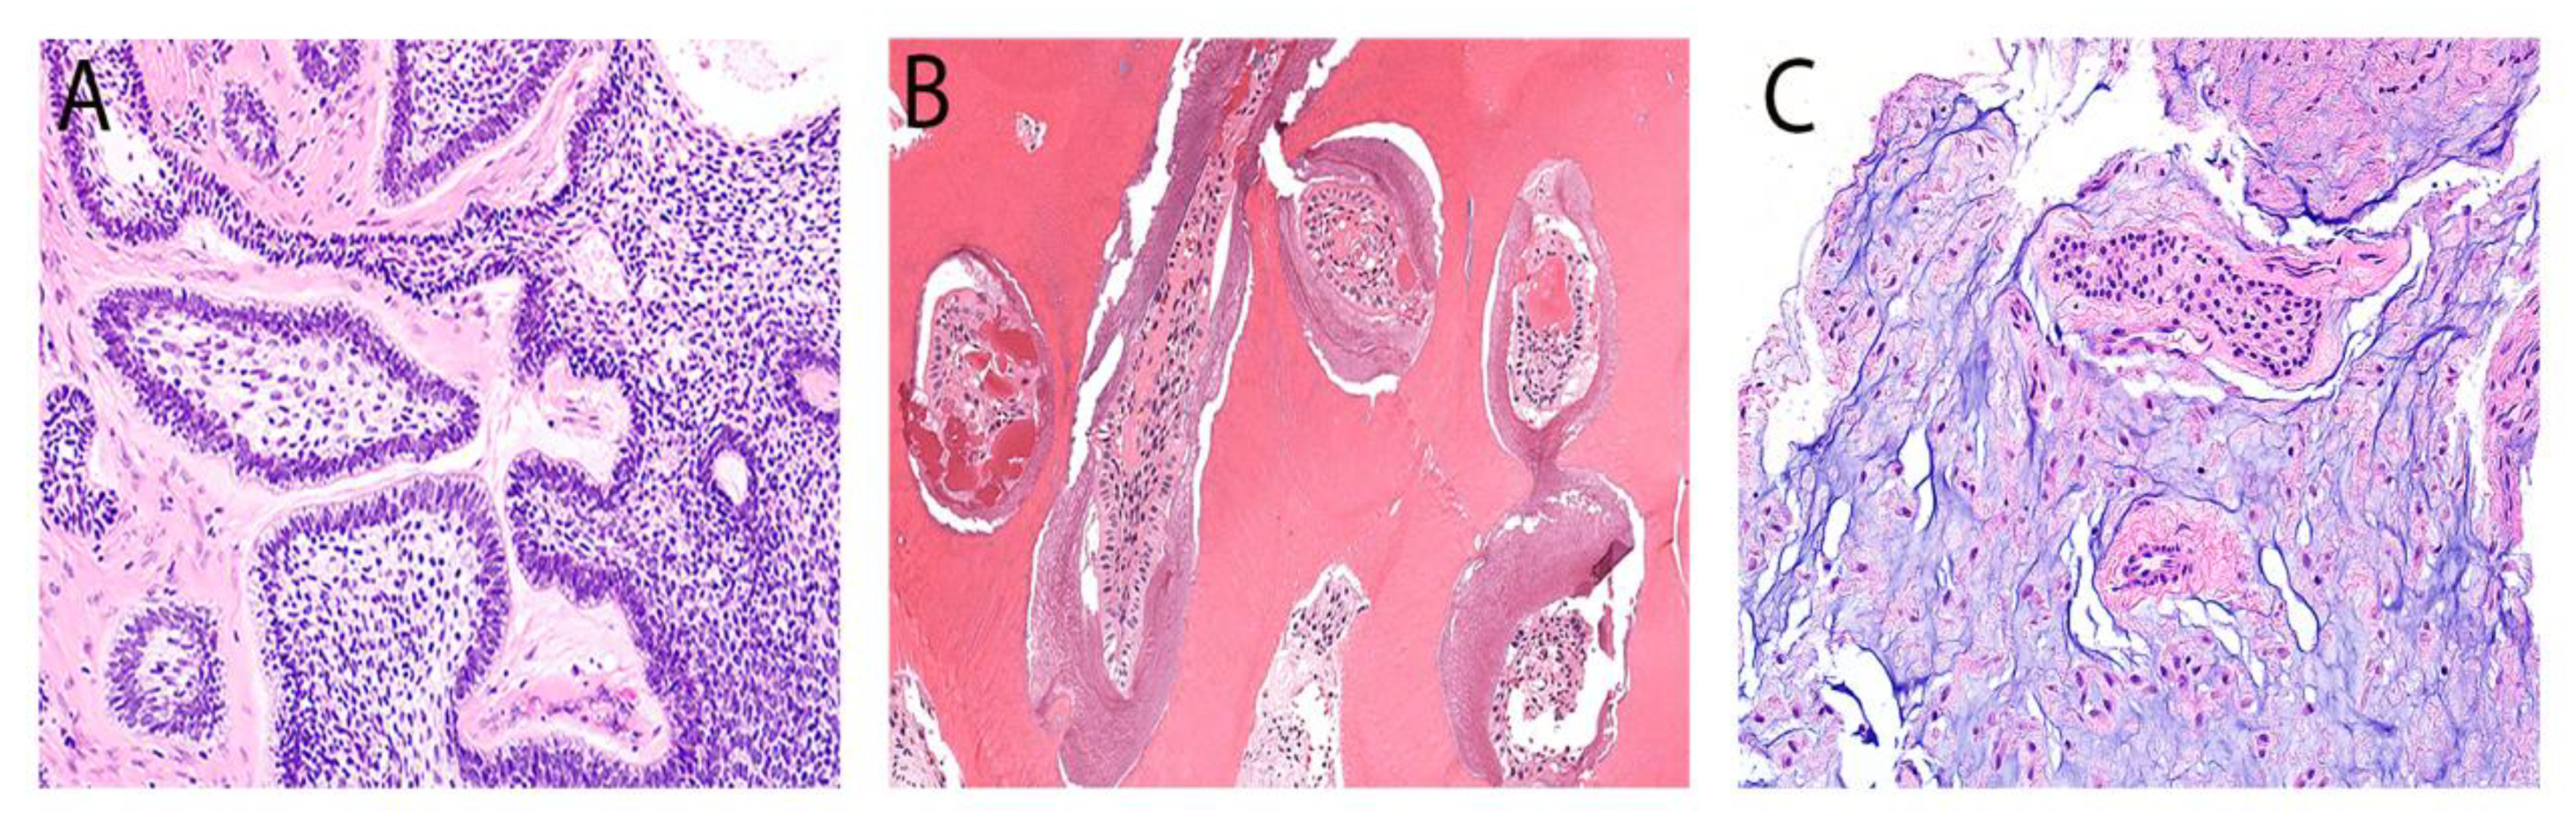

| Primordial odontogenic tumor | POT | Recently described mixed POT exhibiting primitive dental tissue with occasional hard tissue deposition. | Slowly growing lesion in the first two decades and always associated with an unerupted tooth, commonly the third molar. | Well-demarcated, unilocular, bilocular, or multilocular radiolucency associated with an unerupted tooth. |

| Primordial odontogenic tumor | 1 (1.1%) | 1 (100%) | 0 | 0 |

| Primordial odontogenic tumor | 1 (1.1%) | 16 (N/A) | 1 (100%) | 0 | 1 (100%) | 0 |

| Primordial odontogenic tumor | 1 (1.2%) | 0 | 0 | 1 (100%) |